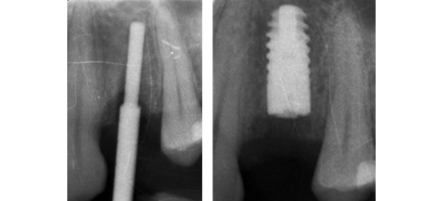

MULTIPLE DENTAL IMPLANT

Dr. Bopanna’s expertise in implantology makes Multiple Dental Implant replacement possible in just three simple steps. His commitment to excellence ensures that your new smile reflects the self-confidence you feel within.

In multiple implants the failing teeth are extracted and implants are placed into extraction sockets just like it’s done for single implants. After allowing the bone and gum to heal around the implant a scan body is attached to the implant/s and a 3d digital impression is taken. The scan is then uploaded to either Atlantis or Exocad and the abutment is designed, after which the stl file(3D file) is used to design the crown which fits on top of the implant. The adoption of advanced technology makes the entire workflow seamless and convenient for patients delivering excellent treatment outcomes. All of these stages can be carried out in the single appointment depending on need and condition of the patient.

FAILING TOOTH

Card image Actual Practice Photographs ©Dr.Pavan Bopanna

IMPLANT PLACEMENT

Card image Card image Card image Card image Card image Actual Practice Photographs ©Dr.Pavan Bopanna

CROWN FITTED